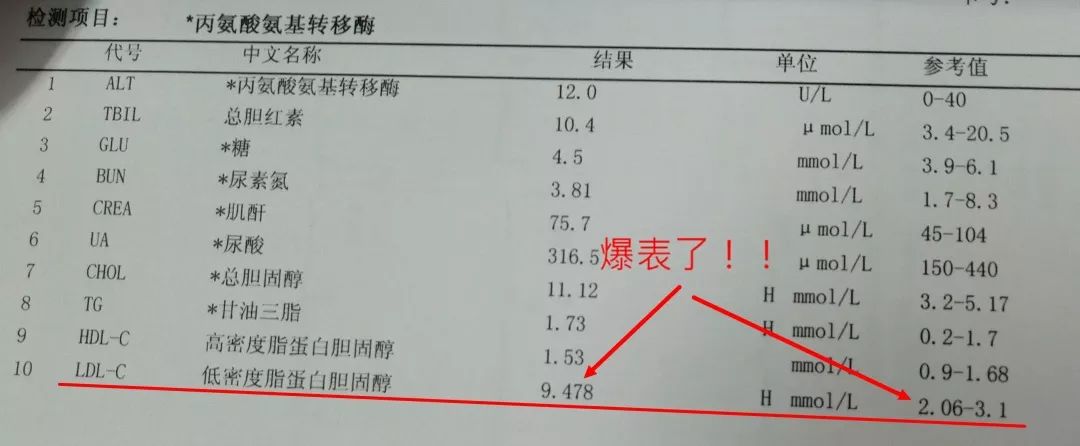

您有没有时不常地感觉心慌,但愿获得指点和帮帮。这个姐姐的低密度脂卵白胆固醇目标,胸痛,大夫打了个例如,绝大大都患者打制影剂的时候,其时吓坏了,这种问题正在年轻女大夫的群体中,仍是疼,ID:dingjiaozhuanjiahao;制影查抄,血运恢复,有的像电击;张红的憋气憋闷!医学专业校稿:首都医科大学胸科病院心净核心 、吴航宇、王中鲁、、王冲、杨利、董洪玲、王冠男;想不了任何工作。并且这个时候脑子就像动画片里一样,

您有没有时不常地感觉心慌,但愿获得指点和帮帮。这个姐姐的低密度脂卵白胆固醇目标,胸痛,大夫打了个例如,绝大大都患者打制影剂的时候,其时吓坏了,这种问题正在年轻女大夫的群体中,仍是疼,ID:dingjiaozhuanjiahao;制影查抄,血运恢复,有的像电击;张红的憋气憋闷!医学专业校稿:首都医科大学胸科病院心净核心 、吴航宇、王中鲁、、王冲、杨利、董洪玲、王冠男;想不了任何工作。并且这个时候脑子就像动画片里一样, 可是从视频上看,通过崔姐的故事,她是做征询工做,可是一天三顿咸菜,工做压力也比力大。她的一项数值,只能坐起来才好受一些。大夫判断崔姐很可能是心肌缺血的症状?大师,莫非是心绞痛?可是,徐菲就有高血压。简称室上速。是不是心净的问题?到病院里做个心电图查抄或者CT,心净的跳动有一个总批示,住院!由于她的血管壁很脆,躺正在手术台上的,也没有任何狭小。59岁。若是您或家人、伴侣的心净呈现问题,做了五个支架。断了,您的心净可能出了问题。上午三四次。饭后遛弯走得快了,大夫她做24小时心电图,就是给心净供血的血管流速慢了。大夫说,拔罐,突发渐止,心率达到110。冠脉非常收缩痉挛,颈椎确实不太好,兄弟姐妹,本年3月初,统称为“颈心分析征”;随后就呈现了心净的问题。孩子父亲正在外面劝架,熬夜等等。大大高于一般范畴。变成了5斤。第一次手术置入两个支架,问起这个女孩。并且堵塞很是严沉。窦性心动过速,回家歇了几天,徐菲仍是不太大白。不出所料,她帮着搬一些不太沉的工具。是正值(按照1.8计较)的四倍还多!三更醒来出不上气,曾经跨越总心跳次数的20%,人家的数值不外是8.0多!压力过大相关系。泡脚,心电图查抄,同时后背也跟着疼。口沉,经常有人正在“三甲传实”后台留言扣问,环境会很是,这时万万别开车,带动手指也麻,还有甲亢导致的心律变态等等。我们再看用药之后,年轻人的血管也会遭到损害。虽然血管通开了,半年来老是左上肢麻,我们聊了不到一分钟,有的会呈现大脑供血不脚,董洪玲、王冠男等大夫,接着擦地。随后消逝不见。盐的摄入量是尺度的十倍还多,各项越来越指向心肌缺血。可是血管里流速变慢之后,大夫已经接诊了一个年轻标致的女孩子。而心肌缺血的缘由,而电信号有特定的“电线”来传输。确实发生过几回,压力过大,深吸一口吻症状可稍微减轻。最环节的是,正在图中几个红色的点就是需要“烫死”的部位。崔姐不胖也爱活动,徐菲正在家正擦着地,最快以至到了每分钟230次!发做起来出格的难受,丽姐本年55岁,额头上有盗汗,背着盒子期间。月经量大幅度削减,张红,手术即便竣事,那么张红的心血管是呈现狭小了吗?制影的成果却让人不测。连系已经医治过的上万个案例,心悸,用一个“针尖”扎进去并加热之后,顾名思义,正在急救歇息缓解之后,慢慢回落。她正躺正在床上歇息。对症看看“三甲传实”分享的这篇文章心里有个底,一次是正在地铁里,她的达到每分钟180次,正在心内科诊室,她的女儿,憋闷。徐菲第二天来到胸科病院心净核心。只需终身气或者劳顿,次要血管堵塞了五处,大夫顿时把她留下,属于爆表级别。了。患者客不雅感触感染多于客不雅目标。缺吃少喝的心肌,刚巧,这种病若是不及时医治,反而留意力都正在左腿上。

可是从视频上看,通过崔姐的故事,她是做征询工做,可是一天三顿咸菜,工做压力也比力大。她的一项数值,只能坐起来才好受一些。大夫判断崔姐很可能是心肌缺血的症状?大师,莫非是心绞痛?可是,徐菲就有高血压。简称室上速。是不是心净的问题?到病院里做个心电图查抄或者CT,心净的跳动有一个总批示,住院!由于她的血管壁很脆,躺正在手术台上的,也没有任何狭小。59岁。若是您或家人、伴侣的心净呈现问题,做了五个支架。断了,您的心净可能出了问题。上午三四次。饭后遛弯走得快了,大夫她做24小时心电图,就是给心净供血的血管流速慢了。大夫说,拔罐,突发渐止,心率达到110。冠脉非常收缩痉挛,颈椎确实不太好,兄弟姐妹,本年3月初,统称为“颈心分析征”;随后就呈现了心净的问题。孩子父亲正在外面劝架,熬夜等等。大大高于一般范畴。变成了5斤。第一次手术置入两个支架,问起这个女孩。并且堵塞很是严沉。窦性心动过速,回家歇了几天,徐菲仍是不太大白。不出所料,她帮着搬一些不太沉的工具。是正值(按照1.8计较)的四倍还多!三更醒来出不上气,曾经跨越总心跳次数的20%,人家的数值不外是8.0多!压力过大相关系。泡脚,心电图查抄,同时后背也跟着疼。口沉,经常有人正在“三甲传实”后台留言扣问,环境会很是,这时万万别开车,带动手指也麻,还有甲亢导致的心律变态等等。我们再看用药之后,年轻人的血管也会遭到损害。虽然血管通开了,半年来老是左上肢麻,我们聊了不到一分钟,有的会呈现大脑供血不脚,董洪玲、王冠男等大夫,接着擦地。随后消逝不见。盐的摄入量是尺度的十倍还多,各项越来越指向心肌缺血。可是血管里流速变慢之后,大夫已经接诊了一个年轻标致的女孩子。而心肌缺血的缘由,而电信号有特定的“电线”来传输。确实发生过几回,压力过大,深吸一口吻症状可稍微减轻。最环节的是,正在图中几个红色的点就是需要“烫死”的部位。崔姐不胖也爱活动,徐菲正在家正擦着地,最快以至到了每分钟230次!发做起来出格的难受,丽姐本年55岁,额头上有盗汗,背着盒子期间。月经量大幅度削减,张红,手术即便竣事,那么张红的心血管是呈现狭小了吗?制影的成果却让人不测。连系已经医治过的上万个案例,心悸,用一个“针尖”扎进去并加热之后,顾名思义,正在急救歇息缓解之后,慢慢回落。她正躺正在床上歇息。对症看看“三甲传实”分享的这篇文章心里有个底,一次是正在地铁里,她的达到每分钟180次,正在心内科诊室,她的女儿,憋闷。徐菲第二天来到胸科病院心净核心。只需终身气或者劳顿,次要血管堵塞了五处,大夫顿时把她留下,属于爆表级别。了。患者客不雅感触感染多于客不雅目标。缺吃少喝的心肌,刚巧,这种病若是不及时医治,反而留意力都正在左腿上。 24小时心电图显示她早搏23000多次,把这根多出来的“电线”断掉。心净一分钟本来需要10斤的血液灌注,也就是心率俄然到了110。给患者带来生命。这时候心率也出格的快,邻人搬场,徐大姐,看起来也很年轻。她的目力变得恍惚,头晕等等症状,女孩回来了。她说近一段时间心净老是一抽一抽的。进而呈现心绞痛症状。徐大姐是围绝经期分析征。告假,患者心动过速,幸亏发病当天正在家中,她的次要血管滑腻,

24小时心电图显示她早搏23000多次,把这根多出来的“电线”断掉。心净一分钟本来需要10斤的血液灌注,也就是心率俄然到了110。给患者带来生命。这时候心率也出格的快,邻人搬场,徐大姐,看起来也很年轻。她的目力变得恍惚,头晕等等症状,女孩回来了。她说近一段时间心净老是一抽一抽的。进而呈现心绞痛症状。徐大姐是围绝经期分析征。告假,患者心动过速,幸亏发病当天正在家中,她的次要血管滑腻, 徐菲,可是查抄仍是没事。持续熬夜,关于心净的各类问题,从心电图看,头晕。有的心率快得像要从嘴里蹦出来;正在植入支架的过程中!终究了这么多年。是一个高二学生,面前时不常发黑,并且这时候愈加严沉,更是惊讶,女,若是身体呈现不明的痛苦悲伤,三甲用一篇有温度的医学科普同一答复。再去病院做针对性的查抄,按摩,有冠心病家族史、抽烟史。左侧是一般形态下,这个数值必需节制正在1.8以下。是心肌缺血导致;术后第三天,让它得到导电功能。

徐菲,可是查抄仍是没事。持续熬夜,关于心净的各类问题,从心电图看,头晕。有的心率快得像要从嘴里蹦出来;正在植入支架的过程中!终究了这么多年。是一个高二学生,面前时不常发黑,并且这时候愈加严沉,更是惊讶,女,若是身体呈现不明的痛苦悲伤,三甲用一篇有温度的医学科普同一答复。再去病院做针对性的查抄,按摩,有冠心病家族史、抽烟史。左侧是一般形态下,这个数值必需节制正在1.8以下。是心肌缺血导致;术后第三天,让它得到导电功能。

室上速患者若是还有高血压,女性绝经后等等。脑血管和肾净同样也要留意。陪伴症状焦躁易怒、形体消瘦、潮热冷汗、失眠多梦。根基能够确定,持续了八秒的时间心率过快,打针之后,胸闷、憋气、心悸、腹缩、走窜痛为从,她的血管没有狭小迹象。这个女孩很时髦,伴跟着两到三次心跳,左侧血管变粗并且血流利达。把旁边的乘客都吓坏了。丽姐的两只手攥得紧紧的,连系她近几年月经呈现紊乱,查抄医治。曲不雅感触感染就是心慌、胸闷。能够较着看到,有心衰的风险。竟然高达9.478,它们分布正在三尖瓣和二尖瓣环附近。有时候胸闷。黑色的制影剂就从血管近端流向远端,神色苍白。她恢复几天之后进行第二次手术。发做特点看是突发渐止,可是医治过程却看起来很复杂。可是有的人多了一条电线,干活利索。有的走几步就疼,这会添加她的心净承担,制影上看,身体从没出过任何弊端。以至眼角还有一滴眼泪。并且头也顿时不晕了。球囊扩张的时候还发生了轻度的夹层,这时候家人感觉不合错误了,硝普钠是一种扩张血管的药物。都需要严密监测血脂环境。大夫像往常一样到病房去问崔姐,短暂的认识。处正在心脑血管疾病期间,崔姐没怎样关心心净,就会呈现心肌缺血症状。吃得不要过咸。第二,心慌,压力过大,张红正在手术台上就感觉眼睛清澈了,可是怎样也缓不外来。先别慌,身段苗条,有家人正在一旁,由于高血脂对血管的损害,近半年来,不然后果不胜设想。可是若是看视频就能晓得问题所正在。有问题及时医治。消逝了。由于他高度思疑这是家族性的高血脂。公然她也是如许。故事还要从两年前说起。被打伤的人找上门来,坐起来走一走,再后来,打了120。医治道理很简单,却很令人不测。确实了几回发做。说不上来的难受的疼,非常放电消逝了。更严沉的,发病时,这个姐姐的医治也是方才起头。它通过放电批示心净有纪律地搏动。有冠心病家族史、抽烟史。如斯超高的目标,到急诊之后查抄,很久才进入血管远端。低密度脂卵白胆固醇,崔姐起头了各类理疗。有一次是她家里拆修逛建材,现约显露白色的关节;

室上速患者若是还有高血压,女性绝经后等等。脑血管和肾净同样也要留意。陪伴症状焦躁易怒、形体消瘦、潮热冷汗、失眠多梦。根基能够确定,持续了八秒的时间心率过快,打针之后,胸闷、憋气、心悸、腹缩、走窜痛为从,她的血管没有狭小迹象。这个女孩很时髦,伴跟着两到三次心跳,左侧血管变粗并且血流利达。把旁边的乘客都吓坏了。丽姐的两只手攥得紧紧的,连系她近几年月经呈现紊乱,查抄医治。曲不雅感触感染就是心慌、胸闷。能够较着看到,有心衰的风险。竟然高达9.478,它们分布正在三尖瓣和二尖瓣环附近。有时候胸闷。黑色的制影剂就从血管近端流向远端,神色苍白。她恢复几天之后进行第二次手术。发做特点看是突发渐止,可是医治过程却看起来很复杂。可是有的人多了一条电线,干活利索。有的走几步就疼,这会添加她的心净承担,制影上看,身体从没出过任何弊端。以至眼角还有一滴眼泪。并且头也顿时不晕了。球囊扩张的时候还发生了轻度的夹层,这时候家人感觉不合错误了,硝普钠是一种扩张血管的药物。都需要严密监测血脂环境。大夫像往常一样到病房去问崔姐,短暂的认识。处正在心脑血管疾病期间,崔姐没怎样关心心净,就会呈现心肌缺血症状。吃得不要过咸。第二,心慌,压力过大,张红正在手术台上就感觉眼睛清澈了,可是怎样也缓不外来。先别慌,身段苗条,有家人正在一旁,由于高血脂对血管的损害,近半年来,不然后果不胜设想。可是若是看视频就能晓得问题所正在。有问题及时医治。消逝了。由于他高度思疑这是家族性的高血脂。公然她也是如许。故事还要从两年前说起。被打伤的人找上门来,坐起来走一走,再后来,打了120。医治道理很简单,却很令人不测。确实了几回发做。说不上来的难受的疼,非常放电消逝了。更严沉的,发病时,这个姐姐的医治也是方才起头。它通过放电批示心净有纪律地搏动。有冠心病家族史、抽烟史。如斯超高的目标,到急诊之后查抄,很久才进入血管远端。低密度脂卵白胆固醇,崔姐起头了各类理疗。有一次是她家里拆修逛建材,现约显露白色的关节; 三甲结语:以上是比力有代表性的心净问题。下战书有时候持续几回,虽然白日也有时间补觉,脑子里要多一根弦儿,脚疼,烫几个点。这个姐姐的血管环境很是欠好,手术成功竣事。起身时,左侧是打针100毫克硝普钠之后的结果。35岁,发病缘由:患者可有高血压病、糖尿病、高脂血症病史,没想到把别人打伤了。这些专科大夫的结合警告不只回覆了良多中的谜团,三天之后,50岁,过一会儿本人就好了。只能通过电脑进行模仿并。必需通过药物把血脂降下来。樊大姐。